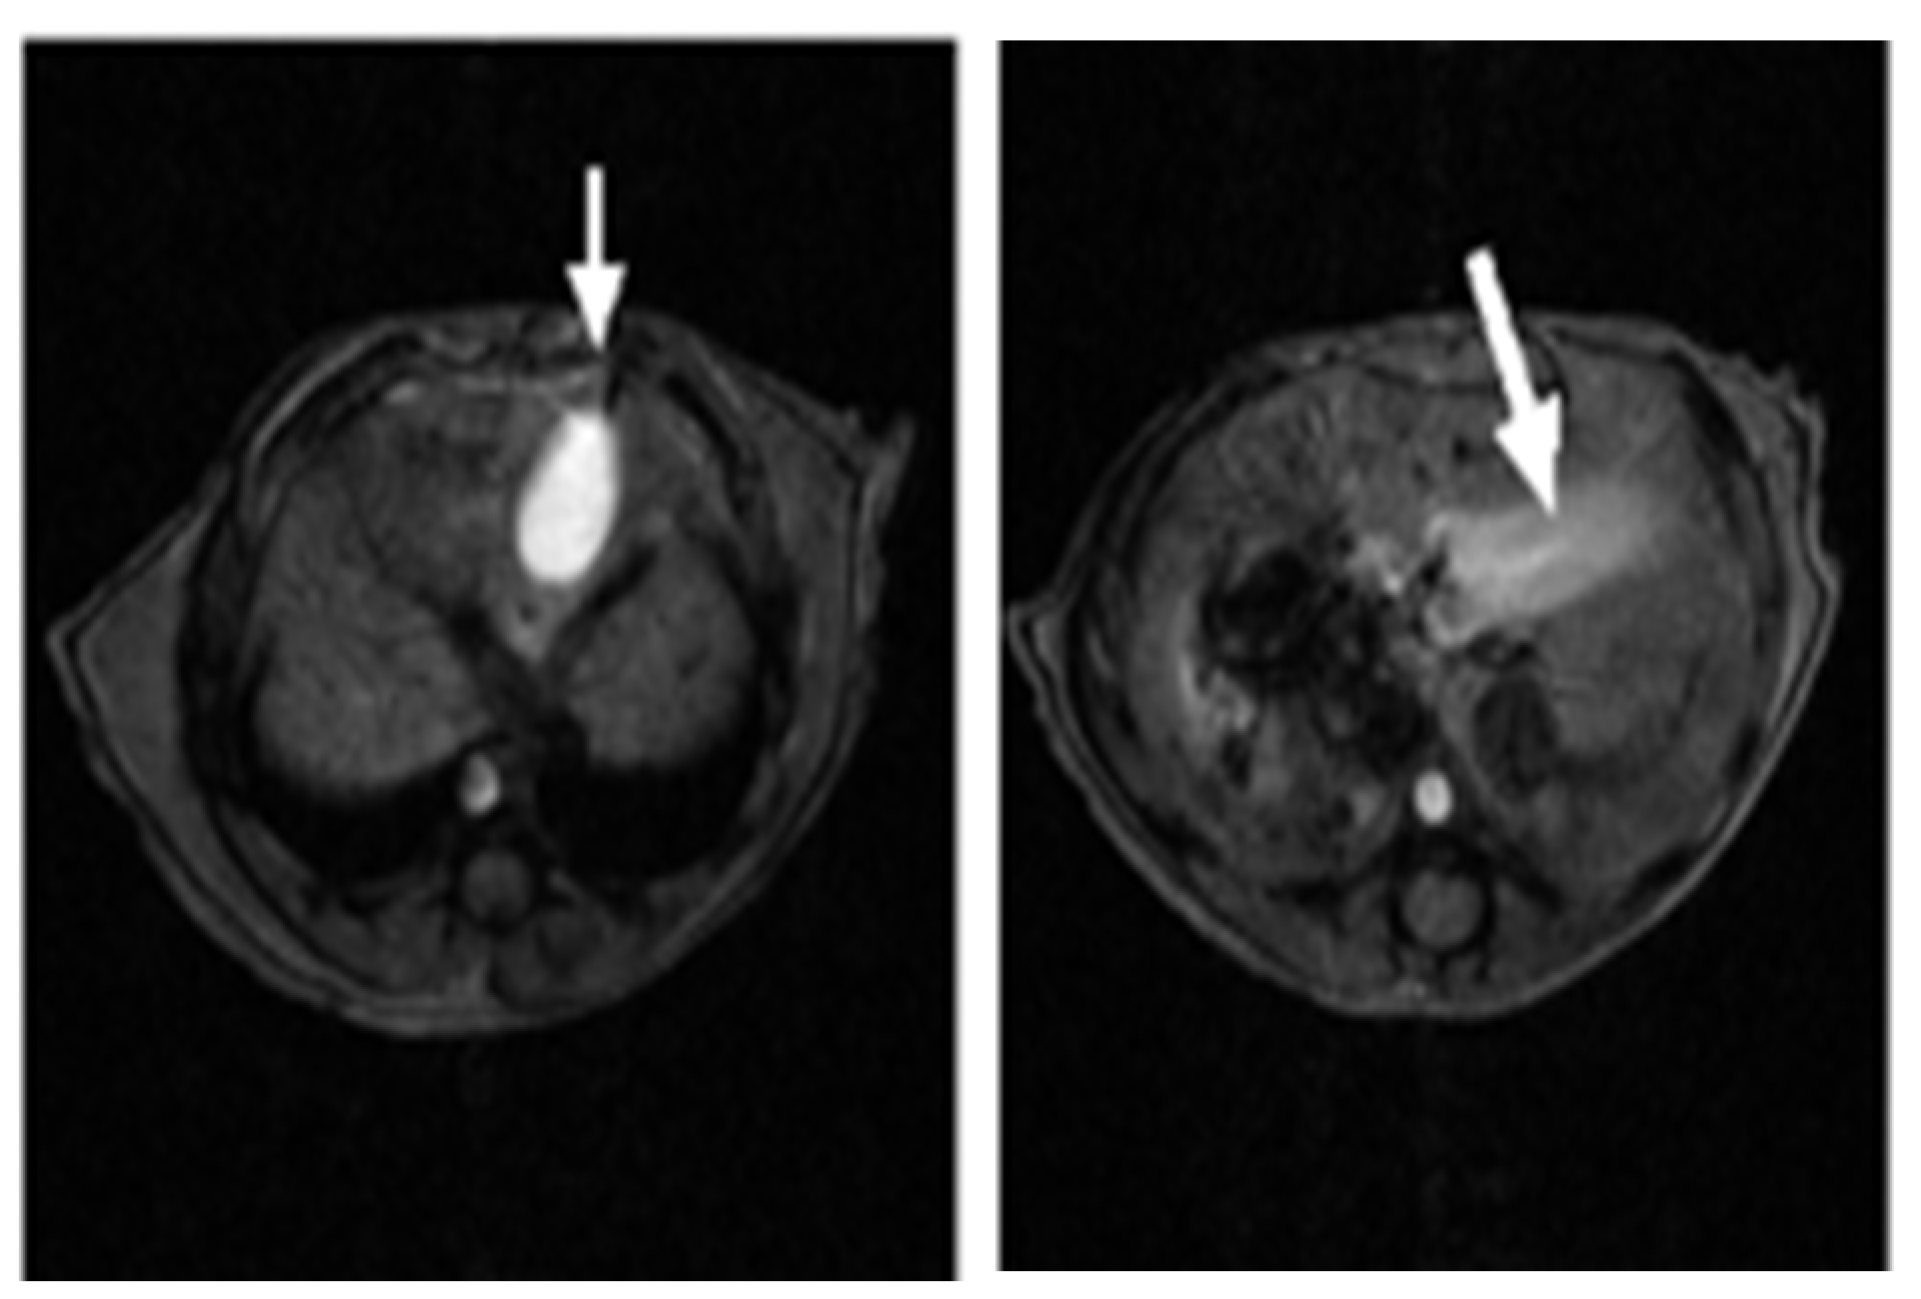

2.1. SV Vectors Can Generate Regression of Human Pancreatic Tumors in an SCID Mouse Model